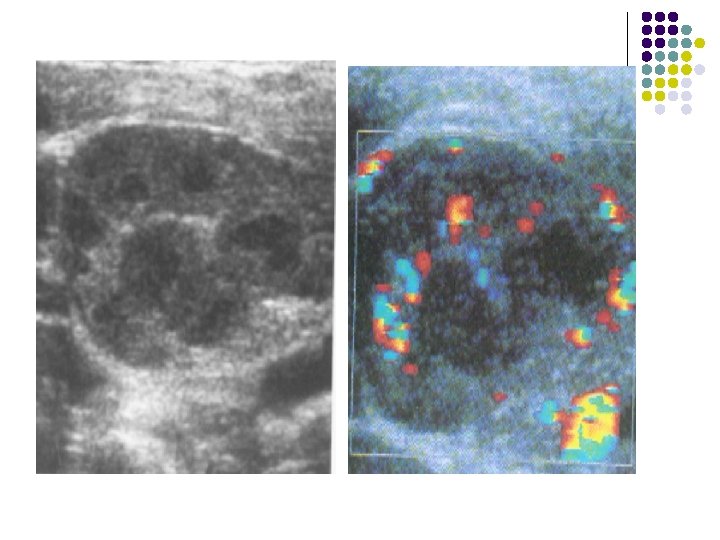

ULTRASOUND: l A well-defined, hypoechoic, cystic structure with posterior acoustic enhancement seen in right illiac fossa. l There is debris posteriorly within this cystic structure.

CT: l There is a bilobed, thin-walled, fluidattenuation mass in the right iliac fossa. l There is some calcification in the posterior wall of this lesion. l l The mass abuts the cecum The appendix is not visualized separately.

IMAGING FEATURES l Plain abdominal film: A well-defined right lower quadrant mass. l Contrast enema: Smooth indentation of the medial aspect of the cecum & non-opacification of the appendix. l Ultrasound: Completely anechoic or hypoechoic with variable internal echogenicity and Whorled appearance is characteristics due to internal contents May have posterior acoustic enhancement. with variable wall thickness and calcification.

l CT: Cystic structures with thin well-defined walls. Contents are usually of homogenous fluidattenuation. Calcification may be noted in the wall. l MR: If the mucocele contains predominantly fluid it will have low signal intensity on T 1 weighted images and high signal intensity on T 2. If, however, the mucocele contains a significant amount of mucin, it will appear hyperintense on both T 1 and T 2 weighted images.